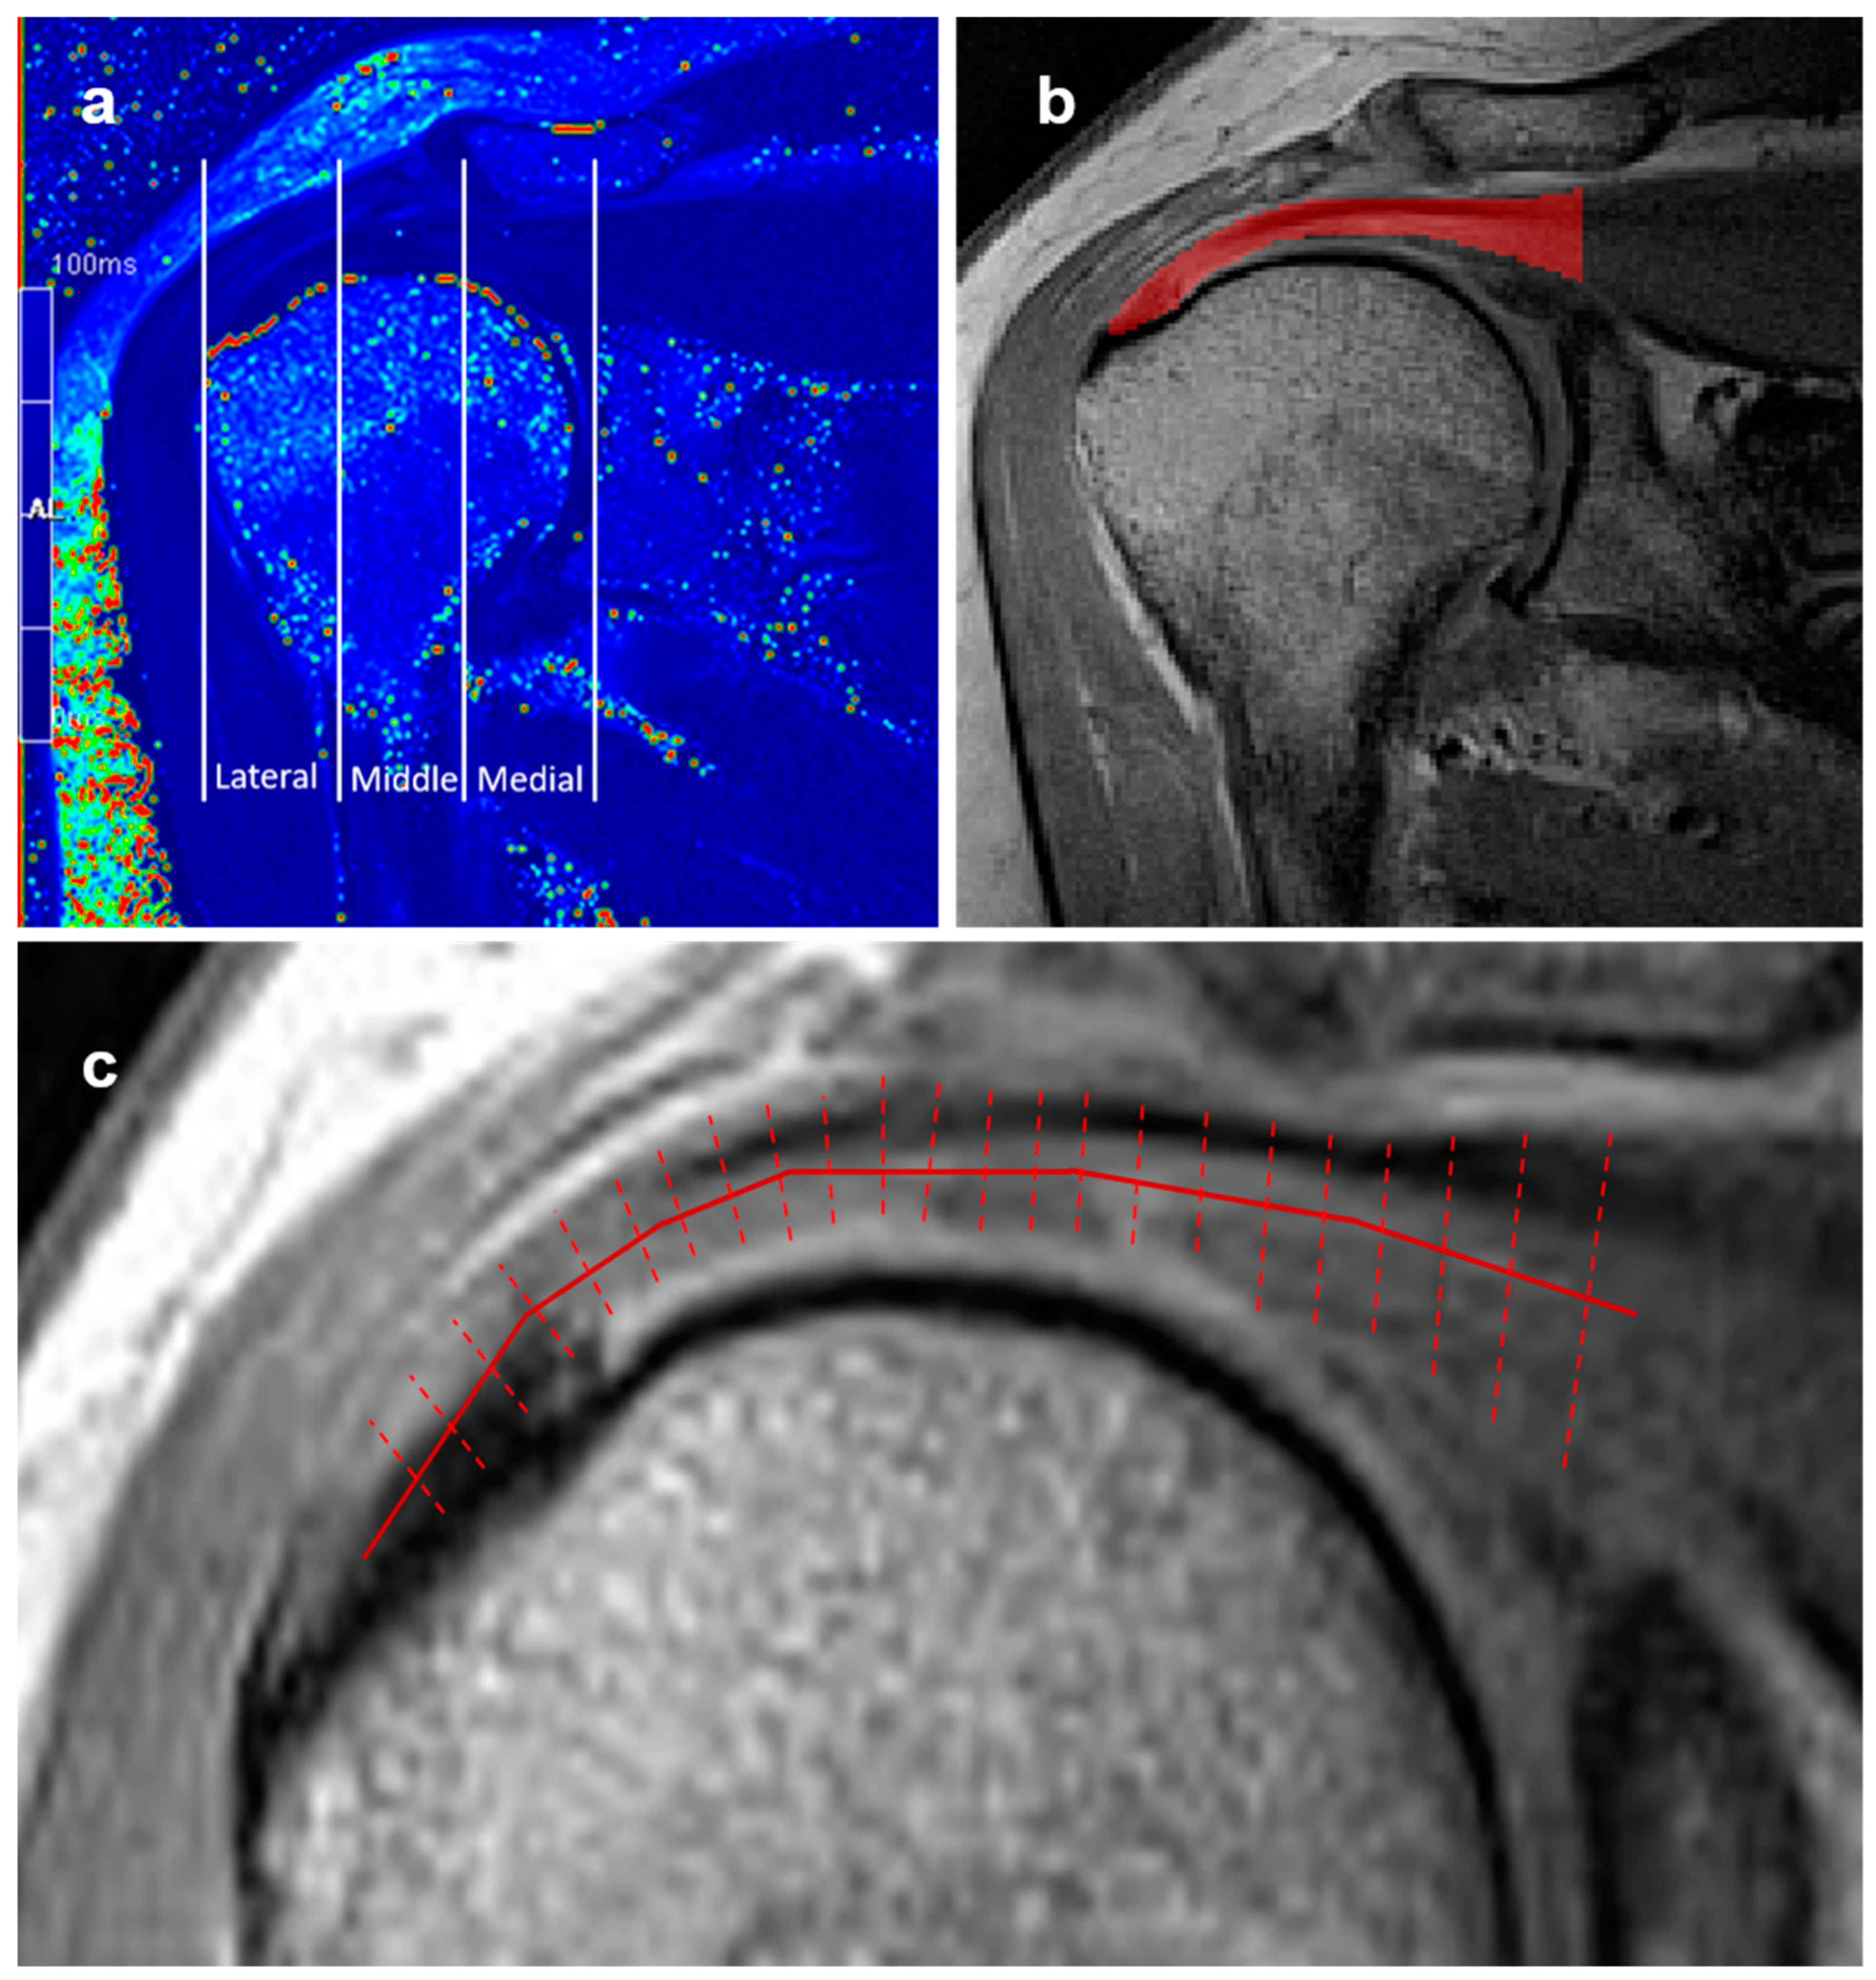

To assess the variability in the T2 values regarding anatomical location along the tendon, the supraspinatus tendons in the T2 maps were further divided into three equivalent segments (lateral, middle, and medial), starting from the footprint of the tendon and ending at the most medial part of the humeral head, as carried out in previous studies [22,23].

The calculated T2 maps of tendons were processed using the R statistical software [24] to obtain T2 value distribution profiles along the tendons from the footprint to the musculotendinous junction. The procedure is illustrated in Figure 2. In order to reduce the impact of noise and the partial volume effects of bone and fluid within the subacromial-subdeltoid bursa on the T2 values of the tendons, the T2 maps were filtered first. Secondly, distributions of the T2 relaxation time profiles were obtained from the average T2 values of all voxels at a given length along the supraspinatus tendon. Finally, T2 distribution profiles were normalized with respect to the tendon length, i.e., the distance from an insertion to the musculotendinous junction. The T2 relaxation time distribution profile of asymptomatic controls with appropriate supraspinatus tendons was carried out in a similar manner to establish reference values for quantitative MRI analysis.

Figure 2.

(a) Coronal T2 map demonstrating division of the supraspinatus tendon into three distinct anatomical segments according to the humeral head: lateral, middle, and medial segments. (b) Manual segmentation of supraspinatus tendon from the footprint of the tendon to the myotendinous junction (encoded in red), where T2 relaxation time analysis was performed. (c) Scheme of supraspinatus tendon T2 relaxation time profiling to obtain distribution of average T2 values along the tendon length.